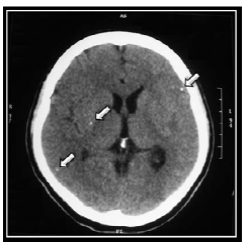

Eleven days after admission, a second brain CT showed supratentorial hydrocephalus, megacisterna magna and three scattered calcifications in both cerebral hemispheres (Figure 1 and 2).